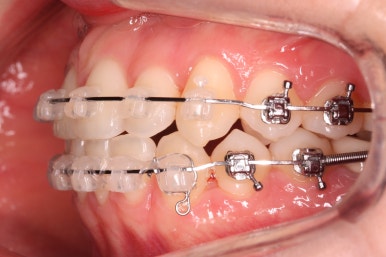

부산부정교합 키다리아저씨치과에 처음 내원하셨을 때의 입안 모습입니다.

위아래 앞니가 삐뚤고 특히 왼쪽 위 송곳니는 밖으로 두드러져 덧니 양상입니다. 윗니는 덧니쪽으로 쏠려 있어서 치열의 중앙이 맞지 않습니다.

전반적인 삐뚤어진 양, 돌출의 느낌, 골격의 비율 등을 고려했을 때 발치 없이 치료를 하기로 했습니다.